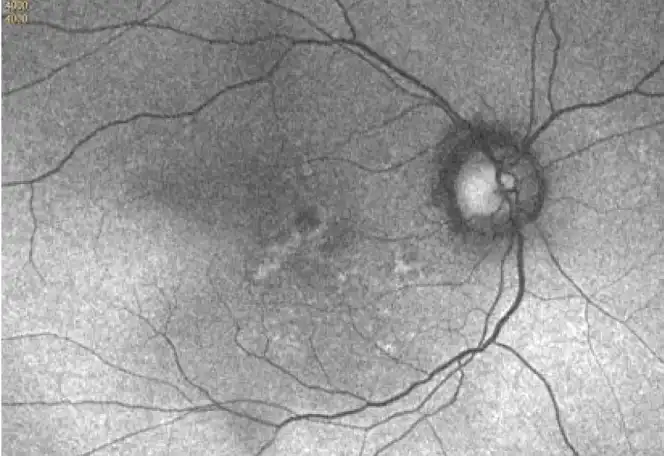

Neovascular AMD

- In clinical trials, use of IZERVAY was associated with increased rates of neovascular (wet) AMD or choroidal neovascularization (7% when administered monthly and 4% in the sham group) by Month 12. Over 24 months, the rate of neovascular (wet) AMD or choroidal neovascularization in the GATHER2 trial was 12% in the IZERVAY group and 9% in the sham group. Patients receiving IZERVAY should be monitored for signs of neovascular AMD.

IZERVAY™ (avacincaptad pegol intravitreal solution) is indicated for the treatment of geographic atrophy (GA) secondary to age-related macular degeneration (AMD)